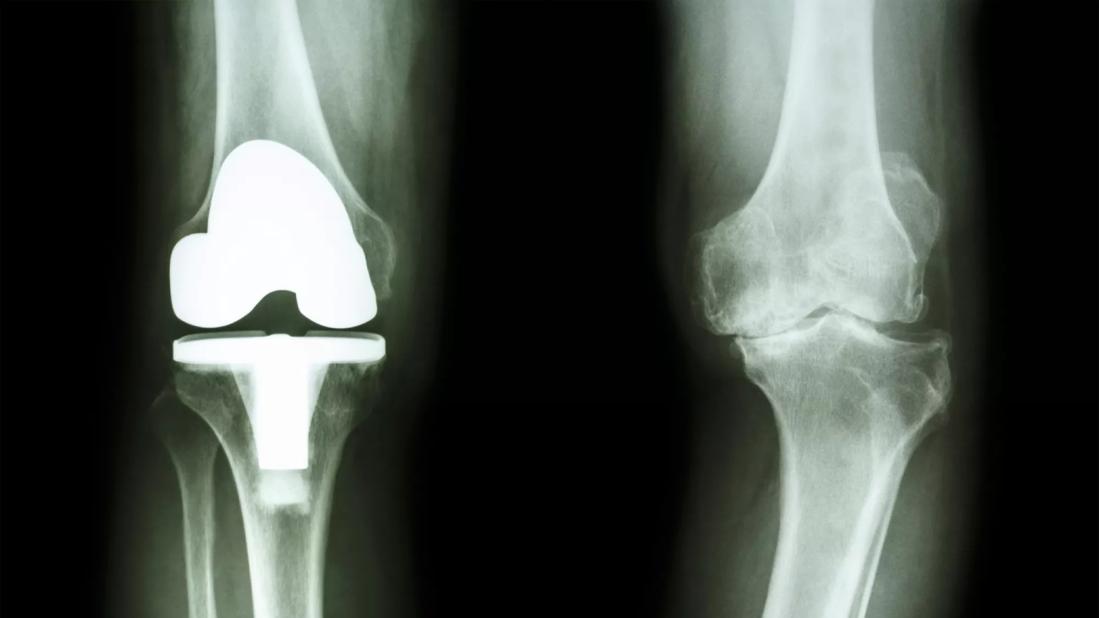

film x-ray of osteoarthritis knee patient and artificial joint

Prosthetic joint infection happens when bacteria around a replaced joint gets infected after surgery. It causes swelling, pain and other more severe problems that if not prevented may require a long-term, painful and costly treatment plan.